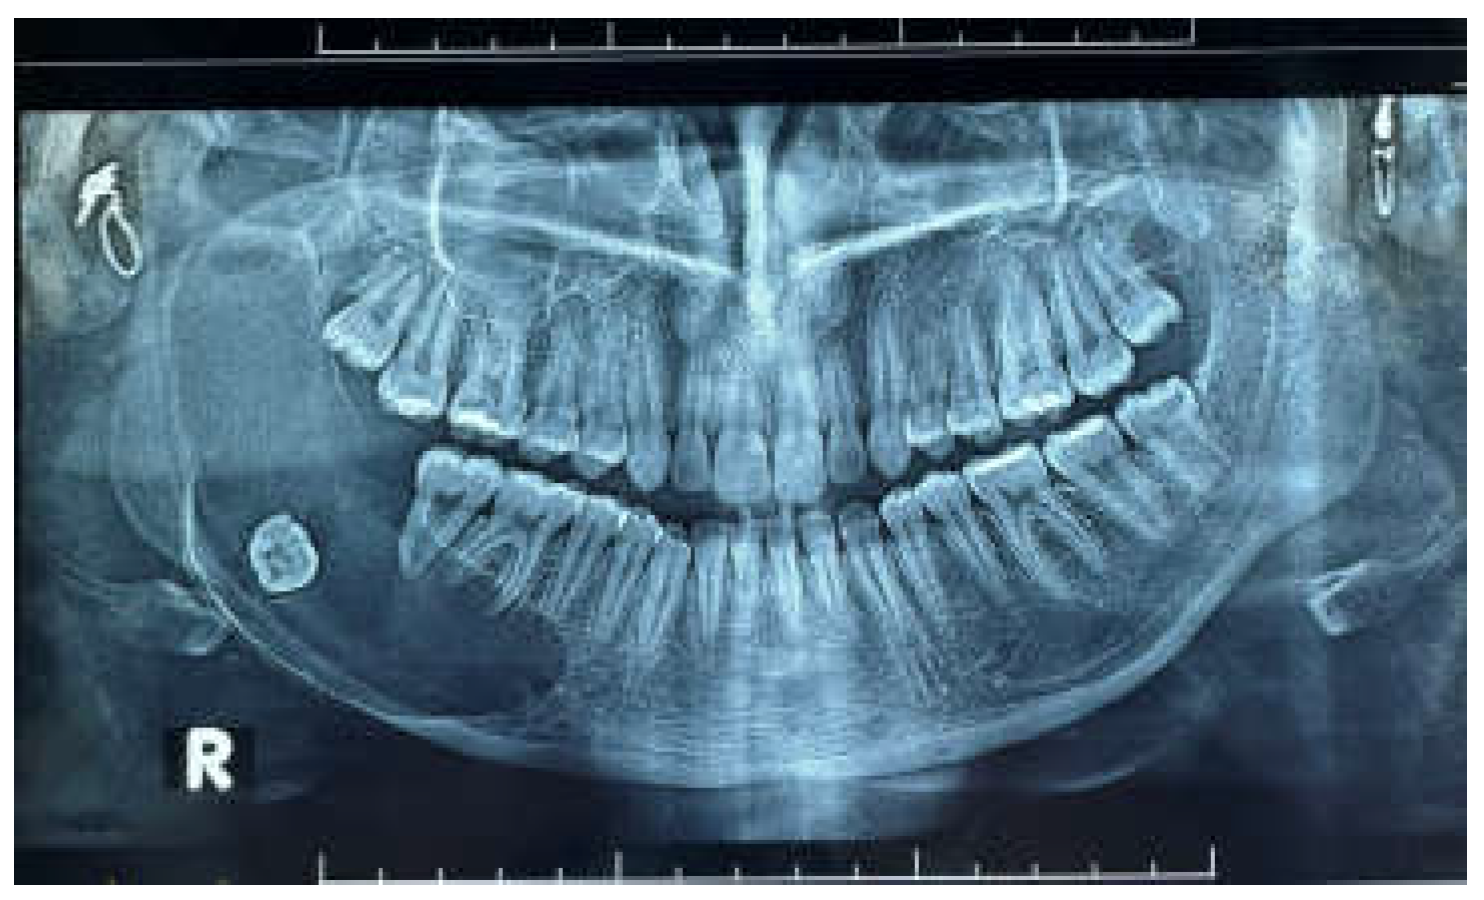

Figure 3. CBCT showing postoperative 2 years of marsupialization.

A 22-year-old female patient reported to our outpatient department with a chief complaint of swelling in the lower right region of the body of the mandible for 4 years. Cone beam CT (CBCT) revealed the extent of the lesion and the loss of cortical bone on both the lingual and buccal sides, along with a thinning of the bone base. Furthermore, the inferior alveolar nerve (IAN) canal was affected and measured approximately 20.5*26.2 cm after previous marsupialization. The patient observed swelling and misalignment of the teeth in the lower right posterior area and reported experiencing pain in that same region. The pain was dull and aching, occurring intermittently, worsening during chewing and easing with rest. During the extraoral examination, a diffuse swelling was noted on the lower third of the face, extending to the right side, measuring about 4 × 4 cm. The skin over the swelling appeared normal, with no visible pulsations or discharge. On palpation, the swelling was firm. The preliminary diagnosis was an odontogenic dentigerous cyst or ameloblastoma. A small sample of the cyst wall was collected for histological analysis. The cystic membrane was marsupialized, and a tube was inserted into the cavity to ensure it remained open. In the first month after surgery, the surgical site was rinsed weekly, followed by monthly follow-up visits at the clinic. The histological report supported a diagnosis of mural unicystic ameloblastoma. The marsupialization procedure was kept in place for three years, during which the cortical rim of the mandibular canal remineralized, and new bone formation and cortical borders developed. A second surgery was scheduled, during which an envelope flap and bone removal—similar to the procedure for impacted tooth extraction—were performed to gain access to the lesion. This approach facilitated the enucleation of the ameloblastoma, involved scraping the bone walls to eliminate any potential ameloblastic infiltrates, and included extensive irrigation with garamycin antibiotics, followed by graft augmentation in the defect. The surgical specimen was sent for histological analysis, and the pathologist confirmed a diagnosis of UA with mural growth.

An panoramic view was conducted 9 months after the excision, showing nearly complete mineralization of the osteolytic area. Additionally, there was significant ossification of the mandibular angle. The patient was monitored for 18 months following surgery. An panoramic view revealed complete healing of the lesion, full ossification of the defect, no signs of recurrence, and preservation of the mandibular angle and ramus profile. Clinically, the treatment resulted in no deformity, no changes to the mandibular contour, and no functional issues. The patient remained symptom-free and showed no significant neurological damage to the inferior alveolar nerve (IAN). However, due to the aggressive nature of this subtype of UA and the potential for recurrence, the patient will continue to be closely monitored with long-term clinical and radiological follow-up. This ongoing supervision will include periodic imaging studies to assess any potential changes in the mandibular area, ensuring early detection of any issues that may arise. Additionally, the healthcare team will provide the patient with guidance on maintaining optimal oral hygiene and overall health to support long-term outcomes.